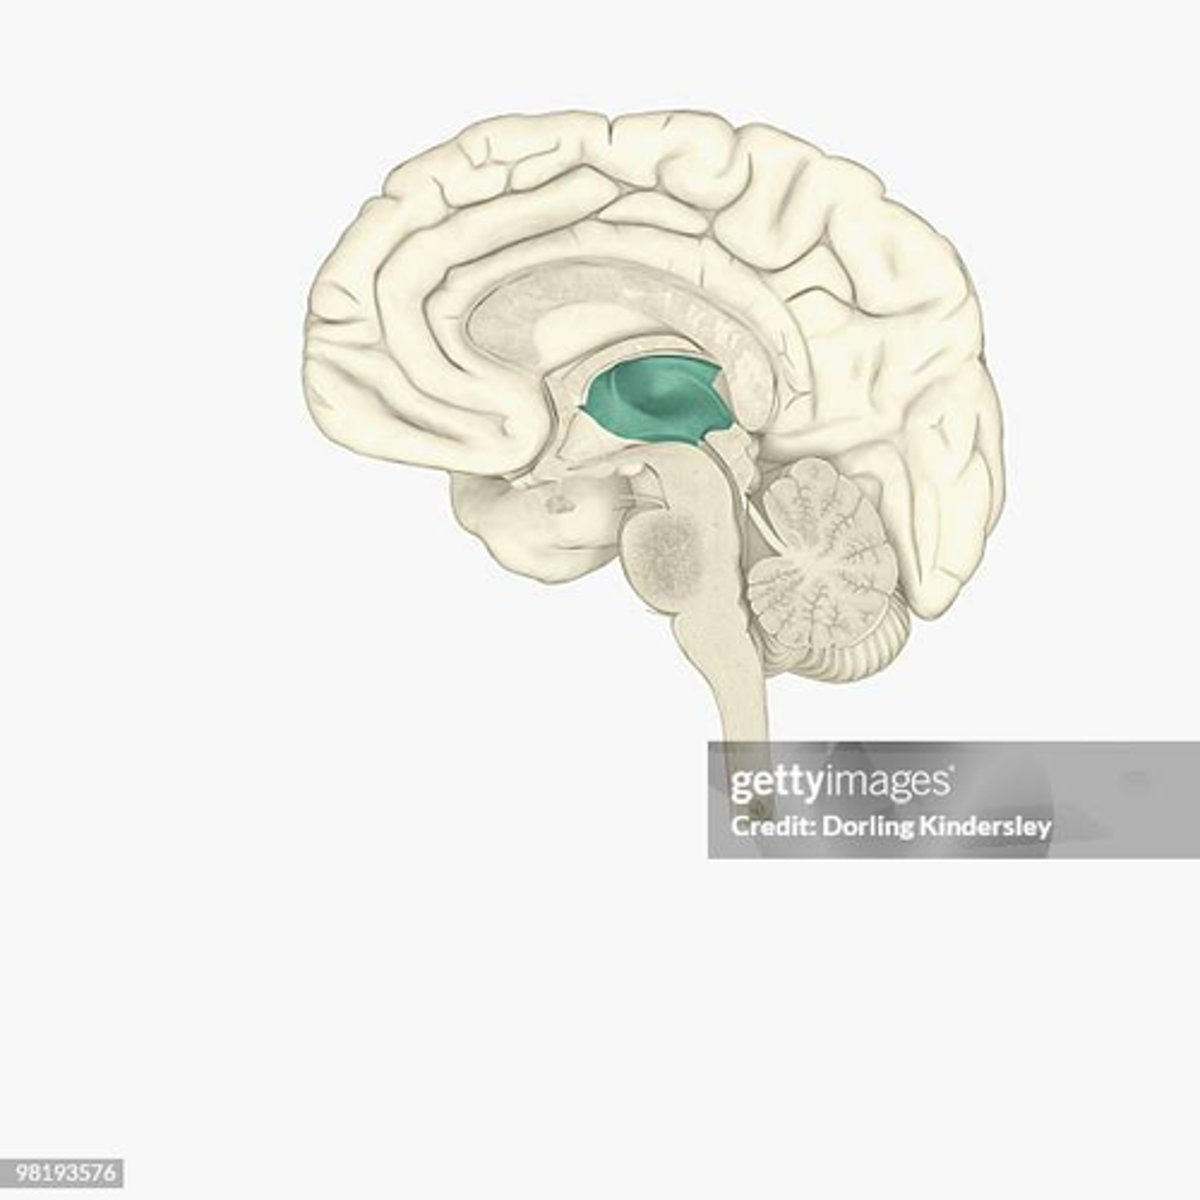

third ventricle